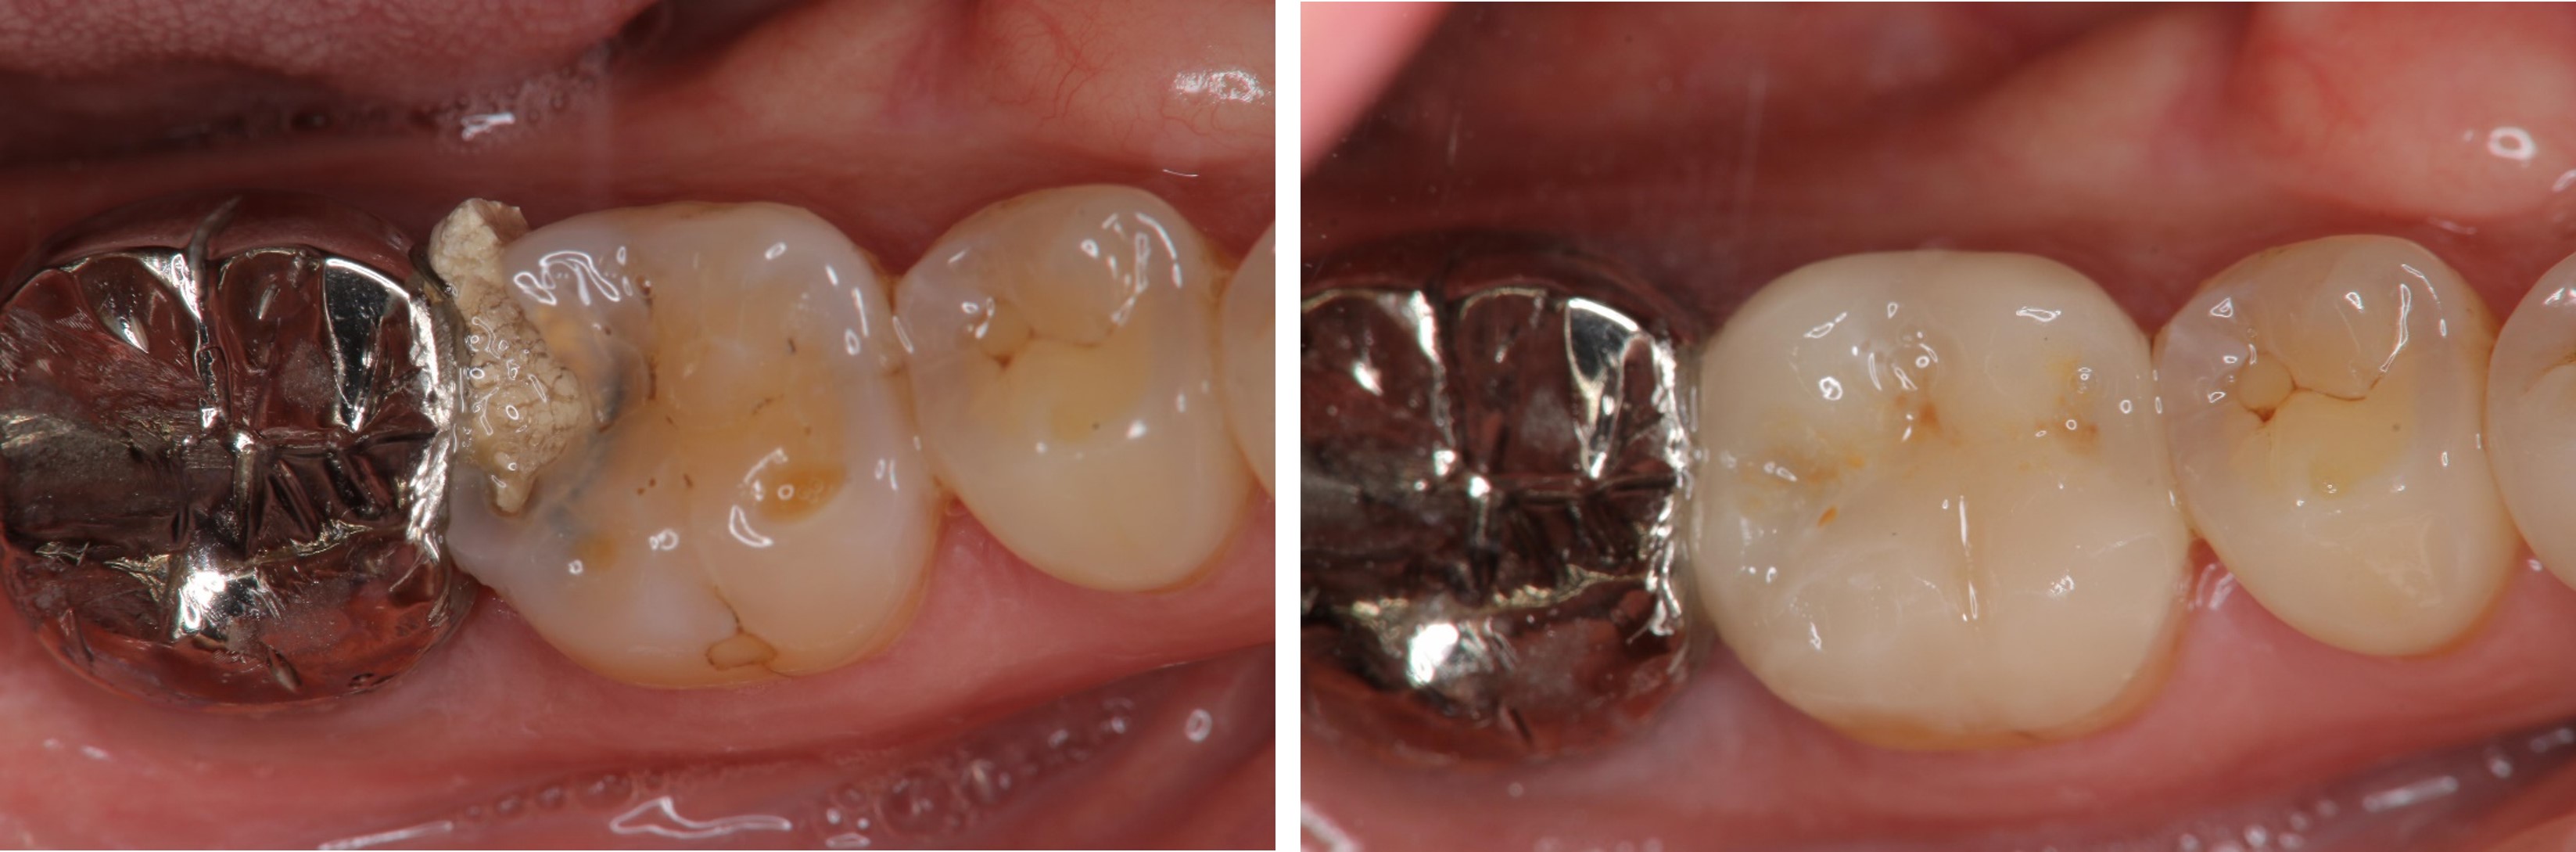

金屬燒付瓷牙合併牙冠增長手術-牙齦下蛀牙-#47

固定式假牙

牙周-膺復合併症